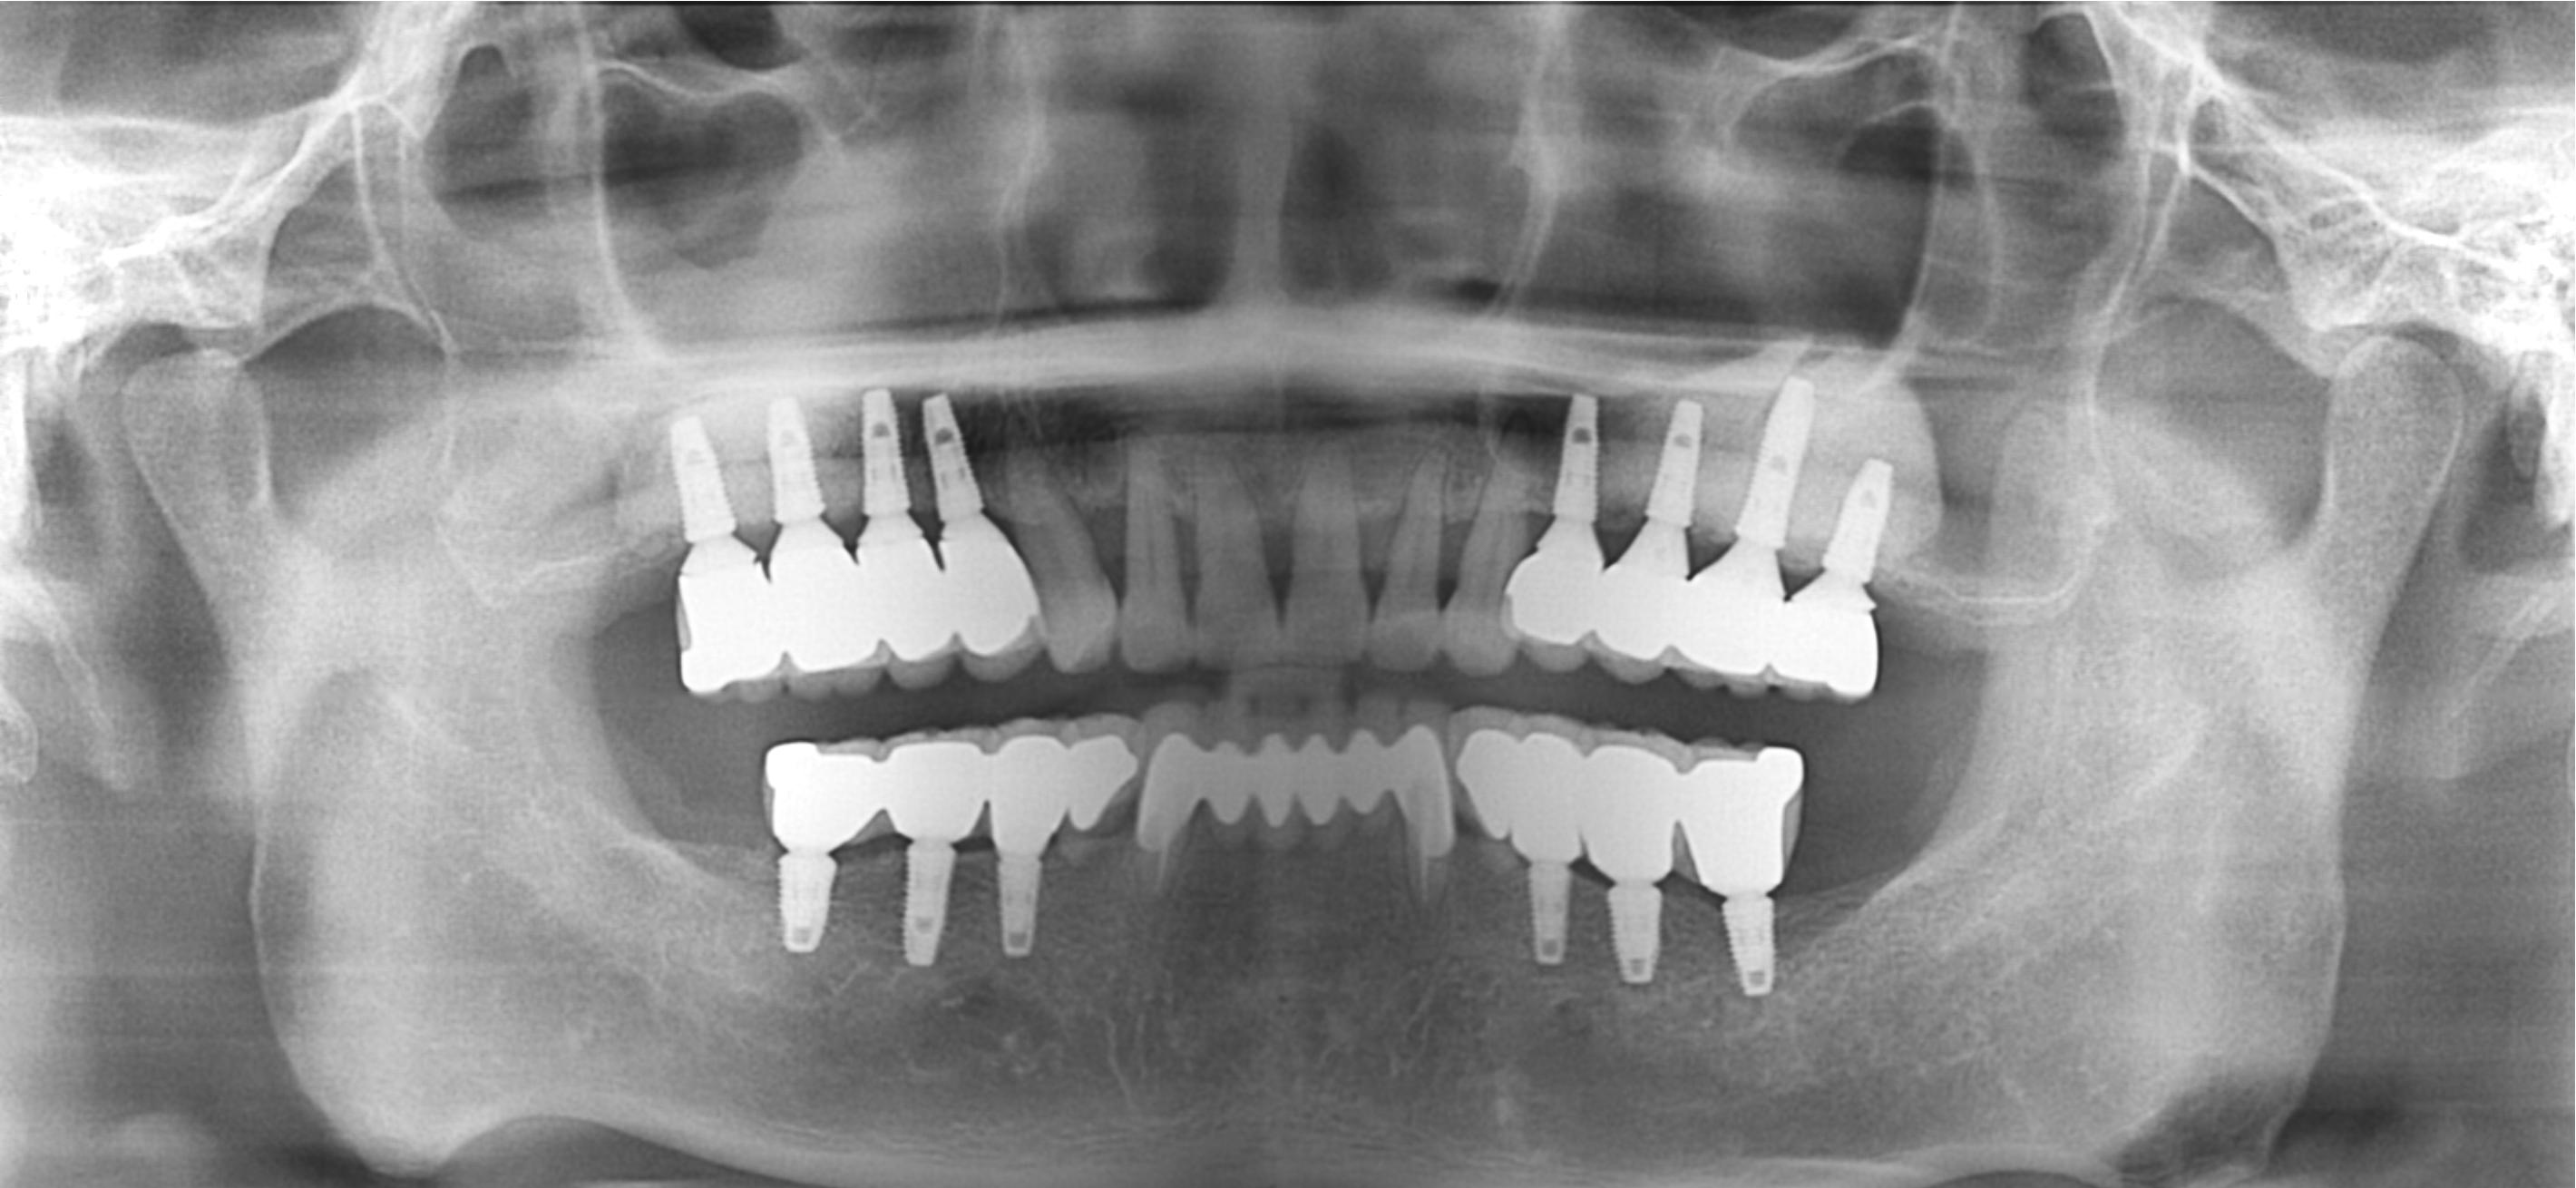

After

상악동거상술 Sinus